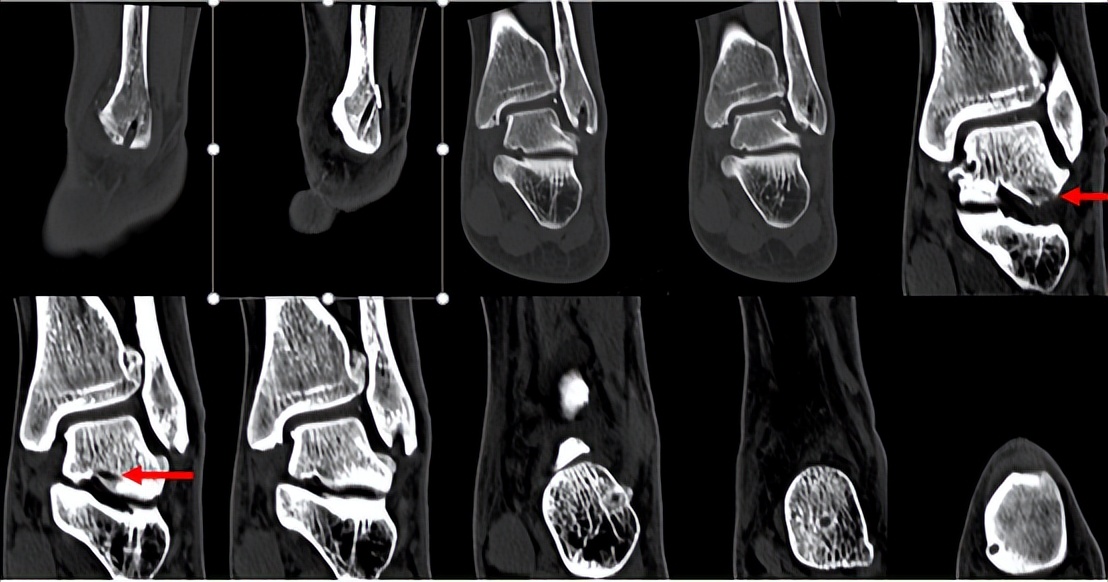

林先生来到省二医后,何河北医生为其进行了详细查体,检查后确诊为踝关节不稳+滑膜软骨瘤。

何河北制定了详细的手术方案,为患者开展踝关节镜下滑膜软骨瘤取出术+距腓前韧带重建术。他从患者踝关节中取出32颗“珍珠”(关节游离体),然后进行踝关节外侧韧带重建。

▲术前可见踝关节前方有大量“珍珠”。

▲术后CT显示滑膜软骨瘤完全取出,韧带重建良好。